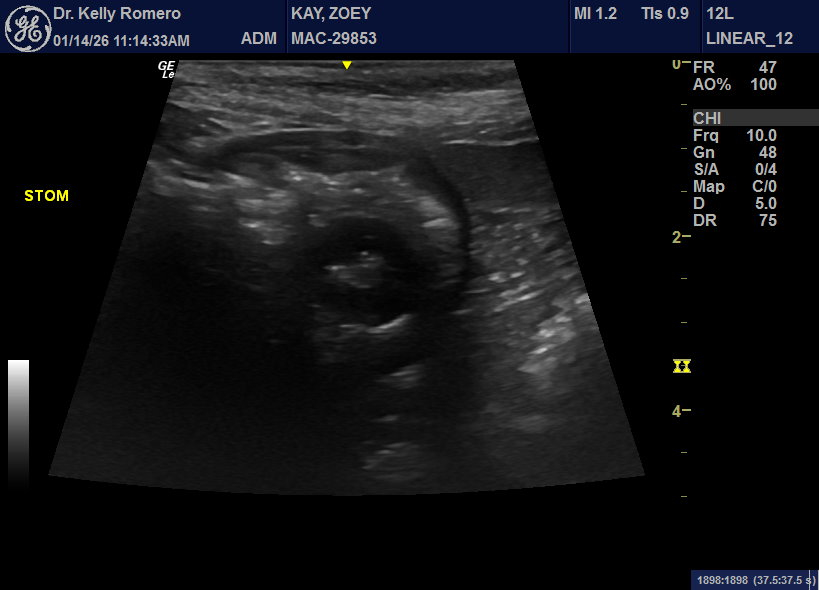

9 year old FS Shepherd cross losing weight, intermittent vomiting, diarrhea that has been worsening now with blood. Do you think these structures in the stomach lumen could be polyps? So far, planning to recommend endoscopy.

Looks like a rubber ball to me but ensure no pill pockets given as they look like this too. If its persistent at npo in followup scan i would cut or scope

Thank you, Eric. It didn’t seem to move in different positions, but the dog is not fully fasted and maybe it is sticking to the wall. Any concerns about the homogenous structure in the body lumen?

Follow up ultrasound – the stomach was empty. Assuming some kind of foreign material that passed